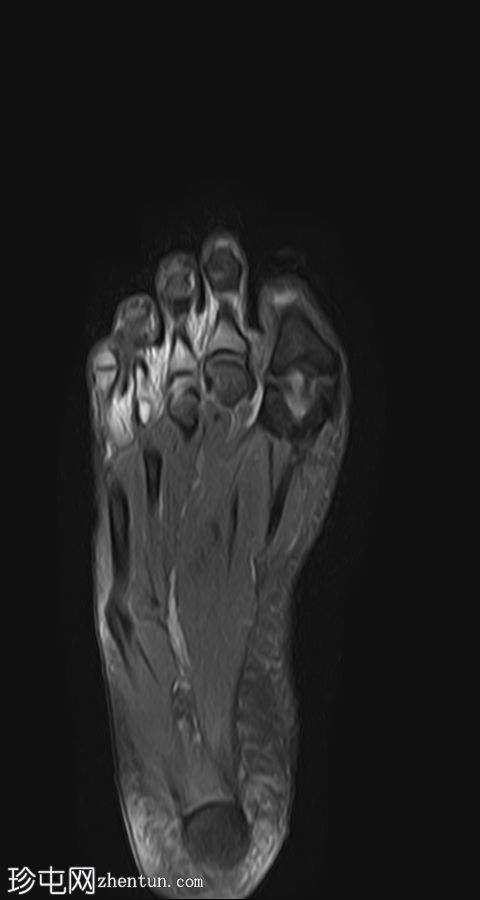

STIR序列

冠状位PD脂肪抑制

质子密度(PD)脂肪抑制像显示第二跖骨干骨髓水肿,伴骨膜及周围软组织水肿。未见明确的皮质骨折线。

第二跖骨应力性骨折,根据Fredericson分级,MRI分级为3级,伴骨膜及周围软组织水肿。